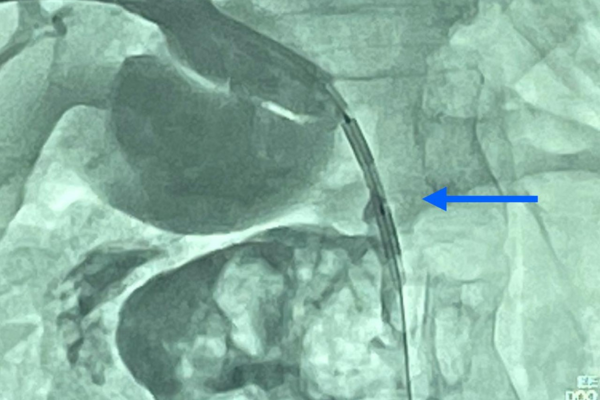

“Uma radiografia de controle realizada 15 dias após a ablação revelou uma desobstrução parcial do canal biliar, demonstrado que esse tratamento poderá se tornar uma alternativa promissora para esse tipo de câncer irressecável (tumor que não pode ser removido cirurgicamente)”, comenta o coordenador da Área Assistencial de Radiologia Intervencionista do HC, Laécio Leitão, um dos responsáveis pelo procedimento.

A alternativa para a melhora da paciente foi o uso de uma nova tecnologia chamada radiofrequência endobiliar, que permite a destruição de células cancerígenas, por meio da elevação da temperatura local. “Esse dispositivo está montado na extremidade de um cateter, que é introduzido através do fígado por um corte de 3 milímetros e guiado por um aparelho de raios-x chamado angiógrafo”, relata Laécio Leitão.

Leitão explica ainda que, num primeiro momento, houve a drenagem do canal biliar obstruído pelo tumor, o que permitiu a melhora da icterícia e da infecção na paciente. Cinco dias depois, foi realizada a ablação (“queimagem”) do tumor por radiofrequência.